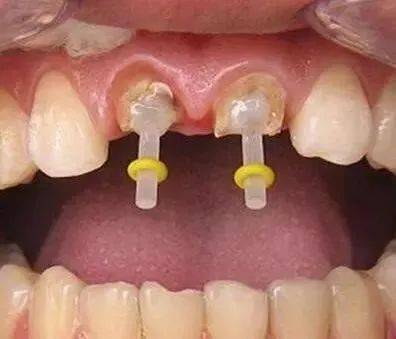

一些人在进行根管治疗后,会进行牙齿打桩。牙齿打桩是指在患者牙齿缺损较大,或因为外伤等原因只剩下牙根时,因剩下的牙齿过短或力量过于薄弱,不能用修复体直接修复,需要给牙根里打桩,加固并延长折断的牙齿,以使假牙能获得足够的力量固定。

牙齿打桩是指插入根管内的部分,利用摩擦力和粘固力、粘接力获得固位,进而为最终修复体提供固位。

牙齿打桩的材料有哪些?

牙齿打桩的材料有纤维桩和金属桩两大类。其中金属桩的材料又分为不锈钢、金钯合金、金铂合金等。如果是前牙,建议使用纤维桩,因为它耐腐蚀性强、不含金属不影响医学检查,不容易引起根折,美观性能好,可以配合全瓷牙适用。而如果是后牙,使用金属桩比较合适,因为处在后牙,对美观的要求性不需要很高,金属桩不易导致牙根折裂,耐腐蚀。